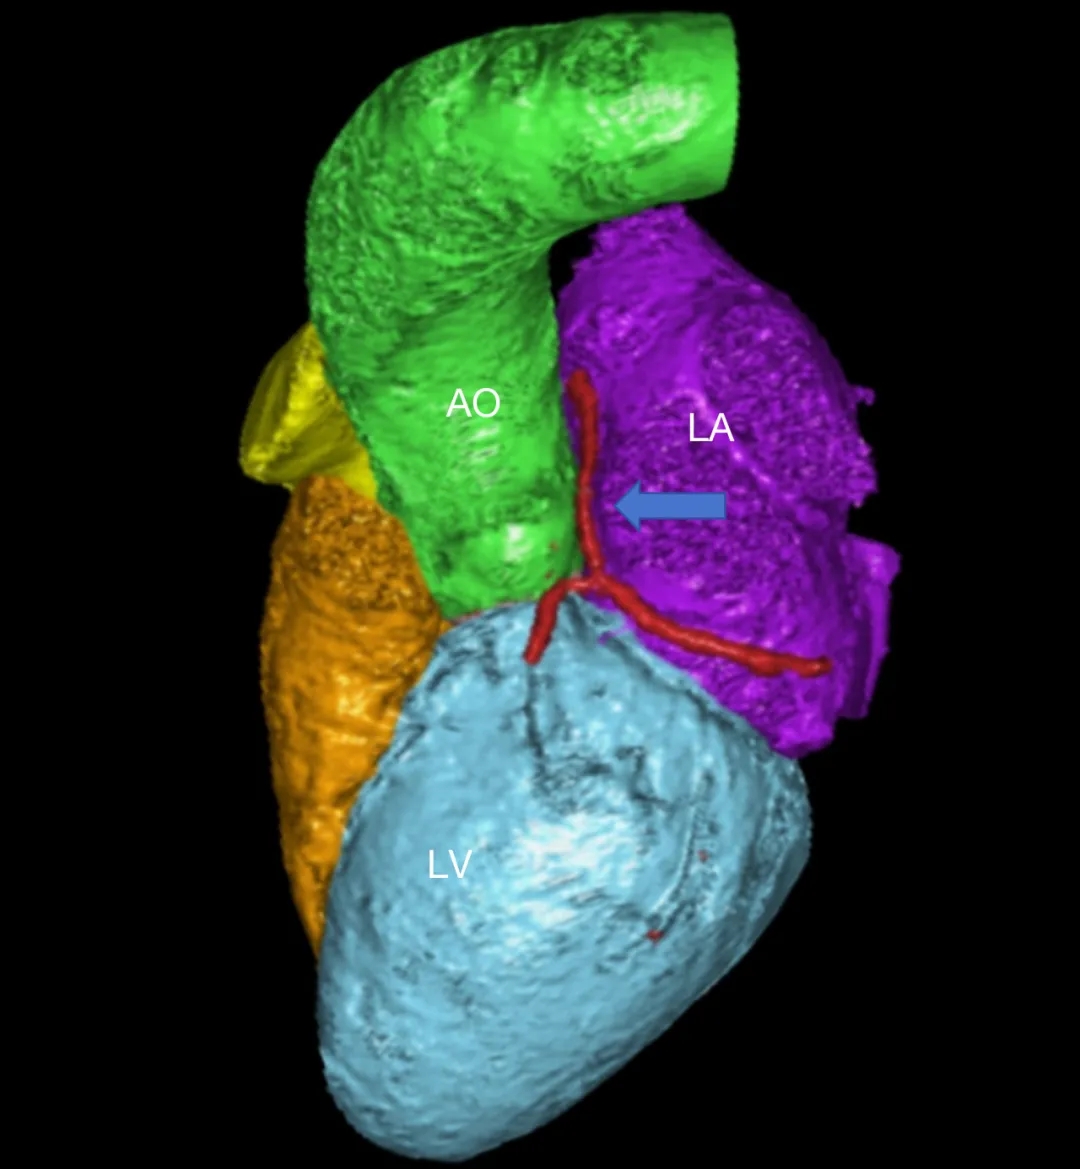

患者女性,27岁,因“卵圆孔未闭相关卒中”入院,拟行介入封堵术。术中MPA1导管跨越卵圆孔进入左心房后送入超滑导丝,发现导丝经由冠状静脉窦走行区回到右心房内,考虑导管进入异常通道,进一步造影可见一起自左心房前壁的冠状静脉分支血管沿房间隔水平横行走行,造影剂最终汇入冠状静脉窦,引流入右心房(图1&2,视频1&2)。该病情血液动力学类似冠状静脉无顶综合征/房间隔缺损,同期行右心导管测肺动脉平均压16mmHg,QP/QS=1.0,排除具有血液动力学意义的左向右分流。由于无法立刻明确单纯封堵PFO的收益与风险,遂终止手术先行完成心脏增强CT明确病变解剖情况,增强CT(图3&4)及重建结果(图5&6)与造影一致,可见一冠状静脉分支起自左心房并沿房间隔走行最终汇入冠状静脉窦。考虑到患者的临床症状可能与PFO以及该异常静脉均存在相关性,且尚不能明确单纯封堵PFO的收益以及同期封堵该静脉的风险,与患者充分沟通后暂时选择最优药物治疗并保持密切随访。

图5